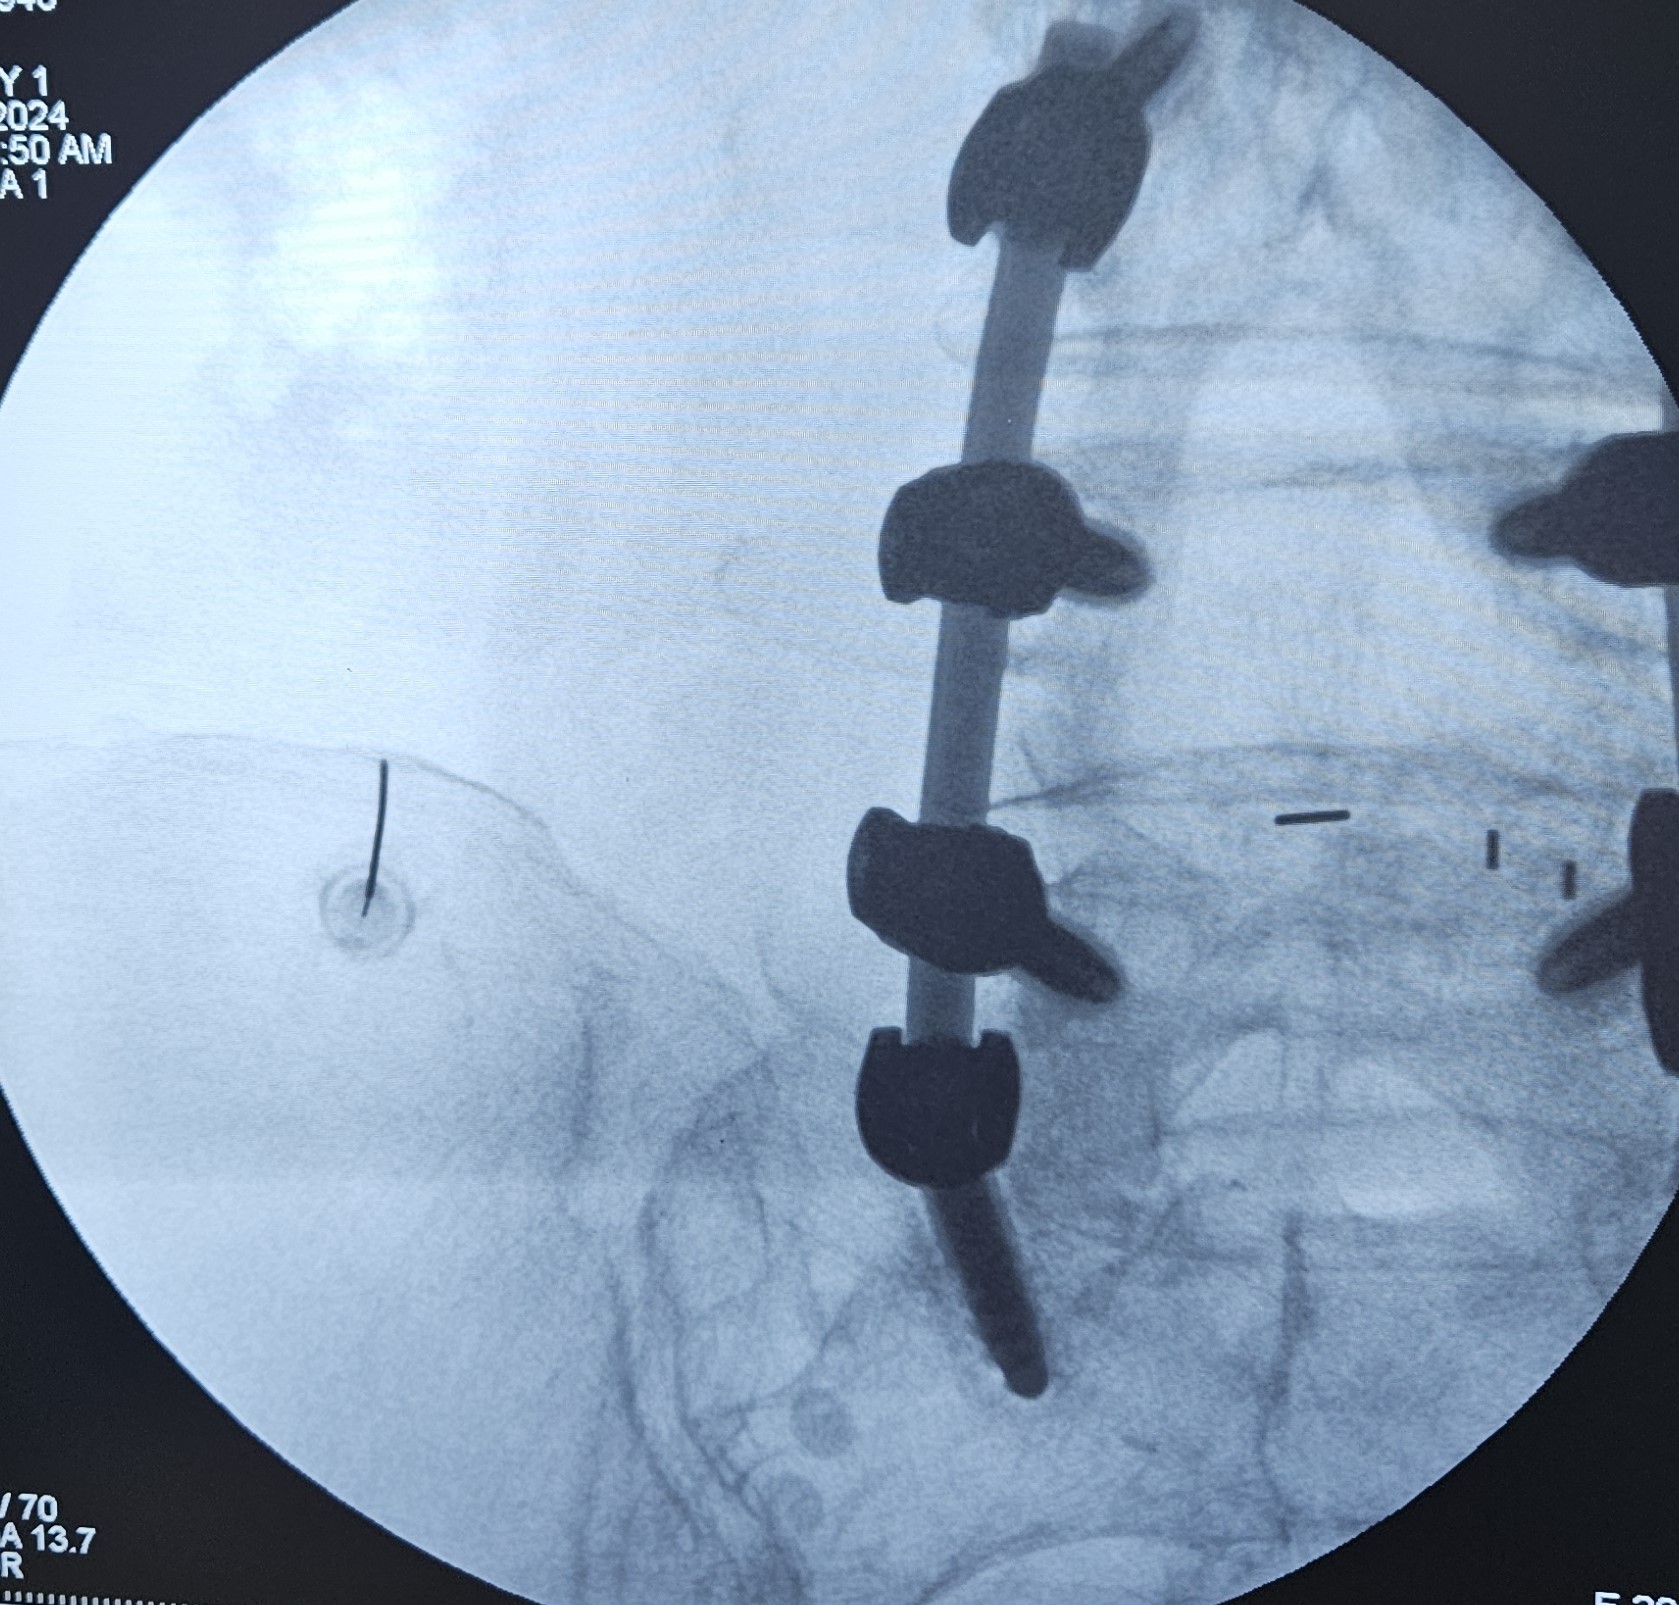

Στην ουραία επισκληρίδιο έγχυση υπό ακτινοσκοπική καθοδήγηση, εισάγεται ένας καθετήρας μέσω του ιερού τρήματος και προωθείται έως το επίπεδο στης κατώτερης οσφυϊκής μοίρας, όπου γίνεται η έγχυση διαλύματος τοπικού αναισθητικού και στεροειδούς.